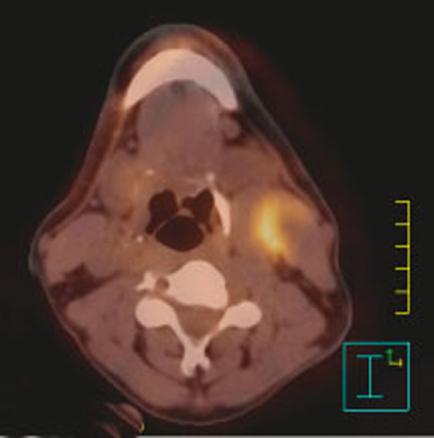

Fixation du fluorodésoxyglucose-(18F) en regard d’un carcinome épidermoïde du sinus piriforme gauche avec une adénopathie tumorale nécrosée sous-digastrique gauche.